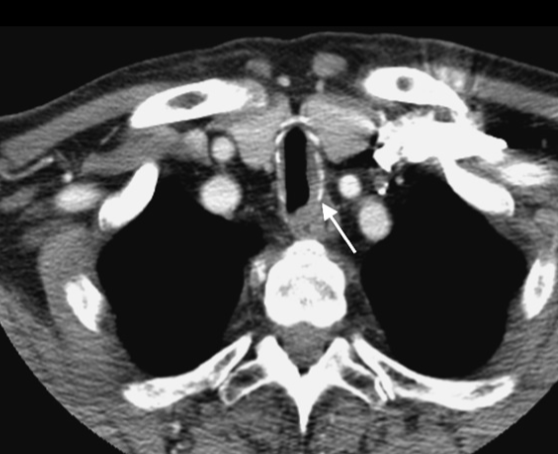

Amyloidose Trachéo-bronchique

- Amyloïdomes dans la paroi muqueuses

- Epaississements nodulaires irréguliers

- Touche les parties cartilagineuses et non cartilagineuses (paroi postérieure++)